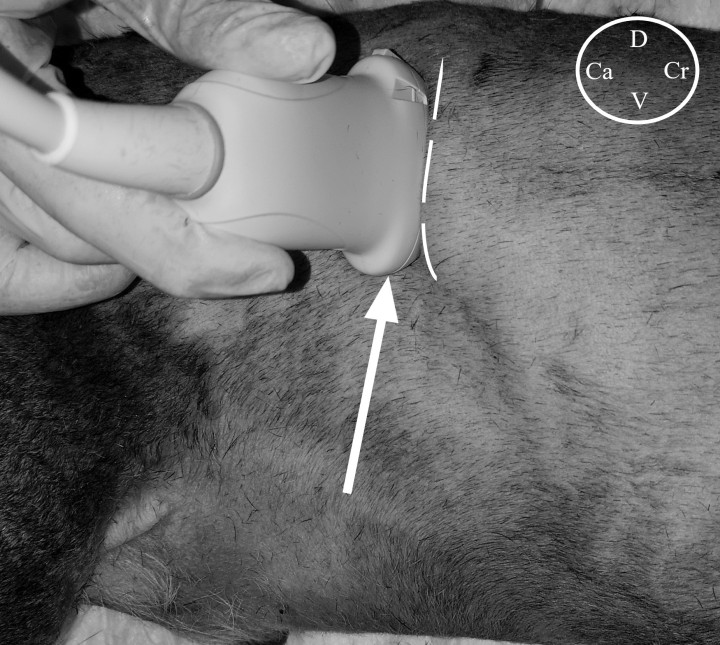

Dado el gran tamaño de la masa, se realizó una tomografía computarizada (TC) con el objetivo de evaluar los límites de la lesión y descartar la posible invasión de la cavidad abdominal. Se realizó una valoración preanestésica previa a la TC que incluyó como pruebas complementarias un hemograma y perfil bioquímico completos, donde no se observaron alteraciones reseñables. Los hallazgos observados tras la TC fueron compatibles con un lipoma infiltrativo (11,5 cm de largo, por 8 cm de ancho y 4,5 cm de altura) que se extendía desde el área de proyección de T12 hasta L6, entre los músculos oblicuo interno y transverso del abdomen (Fig. 1). En el mismo estudio se observaron, de forma accidental, una neoplasia gástrica (Fig. 2) y una lesión hepática, de aspecto quístico y 2,8 cm de diámetro en el lóbulo medial izquierdo. Dados los resultados obtenidos, se amplió el estudio de TC a la región torácica donde no se observaron alteraciones reseñables. Se realizaron citologías de las lesiones hepática y gástrica en las que se obtuvo un resultado compatible con hiperplasia nodular para la lesión en hígado y con leiomioma como diagnóstico más probable en estómago. Se planteó la resección quirúrgica de las lesiones localizadas en pared abdominal y estómago y la toma de biopsias de la lesión hepática. El paciente fue clasificado como ASA III en el momento de la TC y cirugía.

<p>Imagen postcontraste sagital (<strong>A</strong>) y axial (<strong>B</strong>) de TC, en ventana tejido blando, donde se observa una masa ovalada de radiopacidad grasa (flechas) localizada en el flanco izquierdo, entre el músculo oblicuo interno y transverso, y que desplaza algunas vísceras abdominales.</p>

Figura 1

Imagen postcontraste sagital (A) y axial (B) de TC, en ventana tejido blando, donde se observa una masa ovalada de radiopacidad grasa (flechas) localizada en el flanco izquierdo, entre el músculo oblicuo interno y transverso, y que desplaza algunas vísceras abdominales.